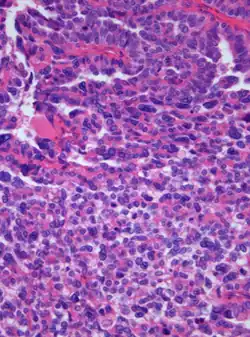

| Photomicrograph of hematoxylin-eosin stained section of a choroid plexus carcinoma (grade III WHO) at 400x magnification | |